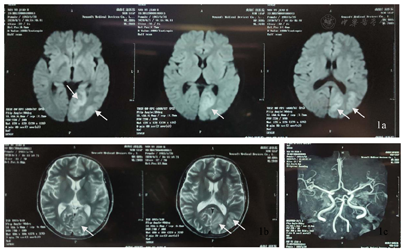

患者,女性,37岁,主因"间断抽搐发作36余年,加重5月余"于2020年11月24日就诊于河北医科大学第二医院神经内科。患者于6月龄时出现抽搐发作,表现为双眼向右上偏斜,四肢抽搐,伴意识不清,呼之不应,持续约数小时缓解。后此症状间断发作,表现同前,每次共3 h左右,发作频率约1次/20 d,共发作3次后未再发作。8月龄时出现发作性肢体活动障碍,表现为哭闹时仅一侧肢体活动,意识清楚,偏瘫侧肢体软,左右侧肢体交替发作,单侧偏瘫持续3天左右交替至另一侧,每次共持续1周左右,发作频率约半个月1次,就诊于当地医院,诊断为"低钙抽搐",给予补钙治疗,症状未见明显好转。1岁半时就诊于北京数家医院,于首都医科大学宣武医院完善头颅CT检查未见明显异常(具体不详),予以口服药治疗(具体不详),服用完后自行停药。后间断就诊于当地医院,诊断为"癫痫",15岁左右开始口服抗癫痫药物(具体不详)。11年前(26岁时)口服卡马西平0.2 g、2次/d,出现发作性肌张力障碍,表现为双上肢伸直,双手腕屈曲外旋,偶伴头眼右偏,意识清楚,为成簇发作,约半个月1簇,3~5 d/簇,数次/d,每次持续约数分钟,月经前或情绪不稳定时易发作;交替性偏瘫发作症状逐渐演变为发作时偏瘫侧肢体伴有强直性肌张力障碍,右侧肢体发作时症状常较左侧重。逐渐停用卡马西平(共服用数月),上述症状仍间断发作,发作表现及频率同前,就诊于北京数家医院,于北京三博脑科医院完善头颅核磁共振、24 h视频脑电图、48h视频脑电图和脑磁图等检查,家属回忆视频脑电图示未见癫痫样放电,头颅核磁共振示有病灶,脑磁图示病灶位置较深不宜手术(因检查结果及报告丢失,具体不详),诊断为"运动障碍性疾病",予以口服美多芭治疗,症状未见好转,数月后自行停用。此后数年间患者除交替性偏瘫发作、肌张力障碍发作外间断于清醒状态下出现全面性强直-阵挛发作2次,发作前有头痛先兆,每次持续约30 min。入院5个月余前患者于清醒状态下突然出现右侧肢体抖动,伴头眼右偏,口角向右侧偏斜,意识丧失,伴流涎,持续约数小时,就诊于当地医院查头颅MR示左侧颞顶枕叶病变,性质待定,后此症状间断发作,偶伴小便失禁,发作前有恶心、呕吐等先兆,发作频率约1次/周,患者逐渐无法自行行走;入院3个月前患者发作形式变化为右手右脚抖动,伴右侧面肌、嘴角抽搐,每次持续约数小时,频率约1次/10 d。现患者口服"丙戊酸钠0.4 g、3次/d,左乙拉西坦每早0.75 g,每晚0.5 g"。个人史:足月顺产,系第一胎第一产,其母亲诉其出生受冻史;运动发育迟缓,6岁会走路;未婚未育,父母及2个妹妹体健。既往史:偏头痛病史20余年,未予诊治;甲状腺功能亢进症病史5年余,口服甲巯咪唑片治疗。月经史、家族史无特殊。入院神经系统查体示神清,智力发育、理解力较差,双瞳孔正大等圆,对光反射稍迟钝,双手肌张力障碍样姿势,右侧肢体肌张力稍高,四肢腱反射(+++),双侧巴宾斯基征(-),余查体不合作。

ATP1A3基因突变可导致生命早期严重癫痫[8]。约半数AHC患者合并癫痫,且多为耐药性癫痫,癫痫发作可与偏瘫发作同时发生或独立出现[2],癫痫类型和癫痫发作类型多样,癫痫发作甚至癫痫持续状态(SE)可以发生在其他类型的AHC发作之前,通常始于新生儿期[9]。携带E815K突变患者通常表现为更严重的AHC表型,癫痫和SE的发生率更高[2,9]。本例患者具备多种癫痫发作类型,常独立出现,多表现为SE,抗癫痫药物反应欠佳。AHC患者影像学表现通常是正常的,少数可出现大脑或小脑萎缩[9,10,11],值得注意的并遗憾的是,本例患者入院前2次于癫痫发作后行头颅MR检查示左侧颞顶枕叶病变,入院后复查头颅MR提示该病变呈可逆性,脑萎缩加重,线粒体环基因及核基因检测未发现突变,最终我们未能明确其性质及原因。国外1项队列研究中观察到1例患者在SE后24 h内进行MRI检查,出现右侧顶叶内侧T2加权液体反转恢复(FLAIR)序列灰质信号增强,并与发作期视频脑电图(EEG)异常及症状学相符,这与本例患者类似[9]。此外该研究还显示AHC患者EEG异常和癫痫样放电的发生率随着监测次数的增加而增加[9]。